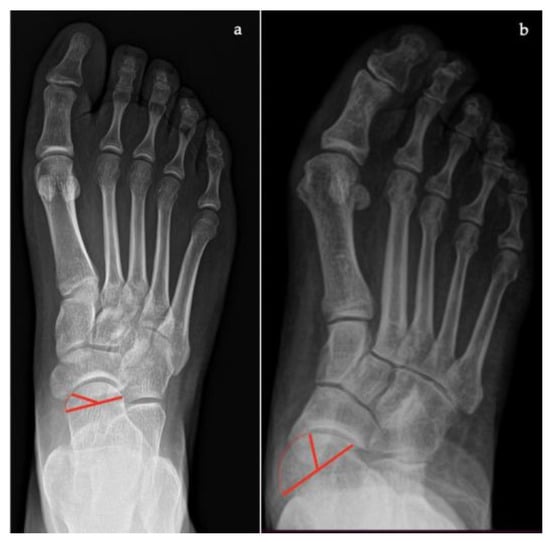

- Talar–first metatarsal angle, between the lines drawn along the long axis of the talus and the first metatarsal (normal 0°, flatfoot: mild >4°, moderate >15°, severe >30°) (Figure 1);

- Talonavicular coverage angle, between the line that joins the medial and lateral articular margins of the talus, and the line that joins the medial and lateral articular margins of the navicular, it represents forefoot abduction (normal, <7°; flatfoot, >7°) (Figure 2);

- Talonavicular uncoverage percentage, the percentage of the talus that is not in contact with the navicular medially, useful to evaluate forefoot abduction (normal, 10% to 30%; flatfoot >30%) (Figure 3);

- Talar incongruency angle (normal, 5° = –26°; flatfoot >26°), is formed by the intersection between a line from the most lateral point of the articular surfaces of the talus and the navicular, and a line from the lateral aspect of the talar neck (in its most narrow segment) to the lateral point of the talar articular surface (Figure 4).